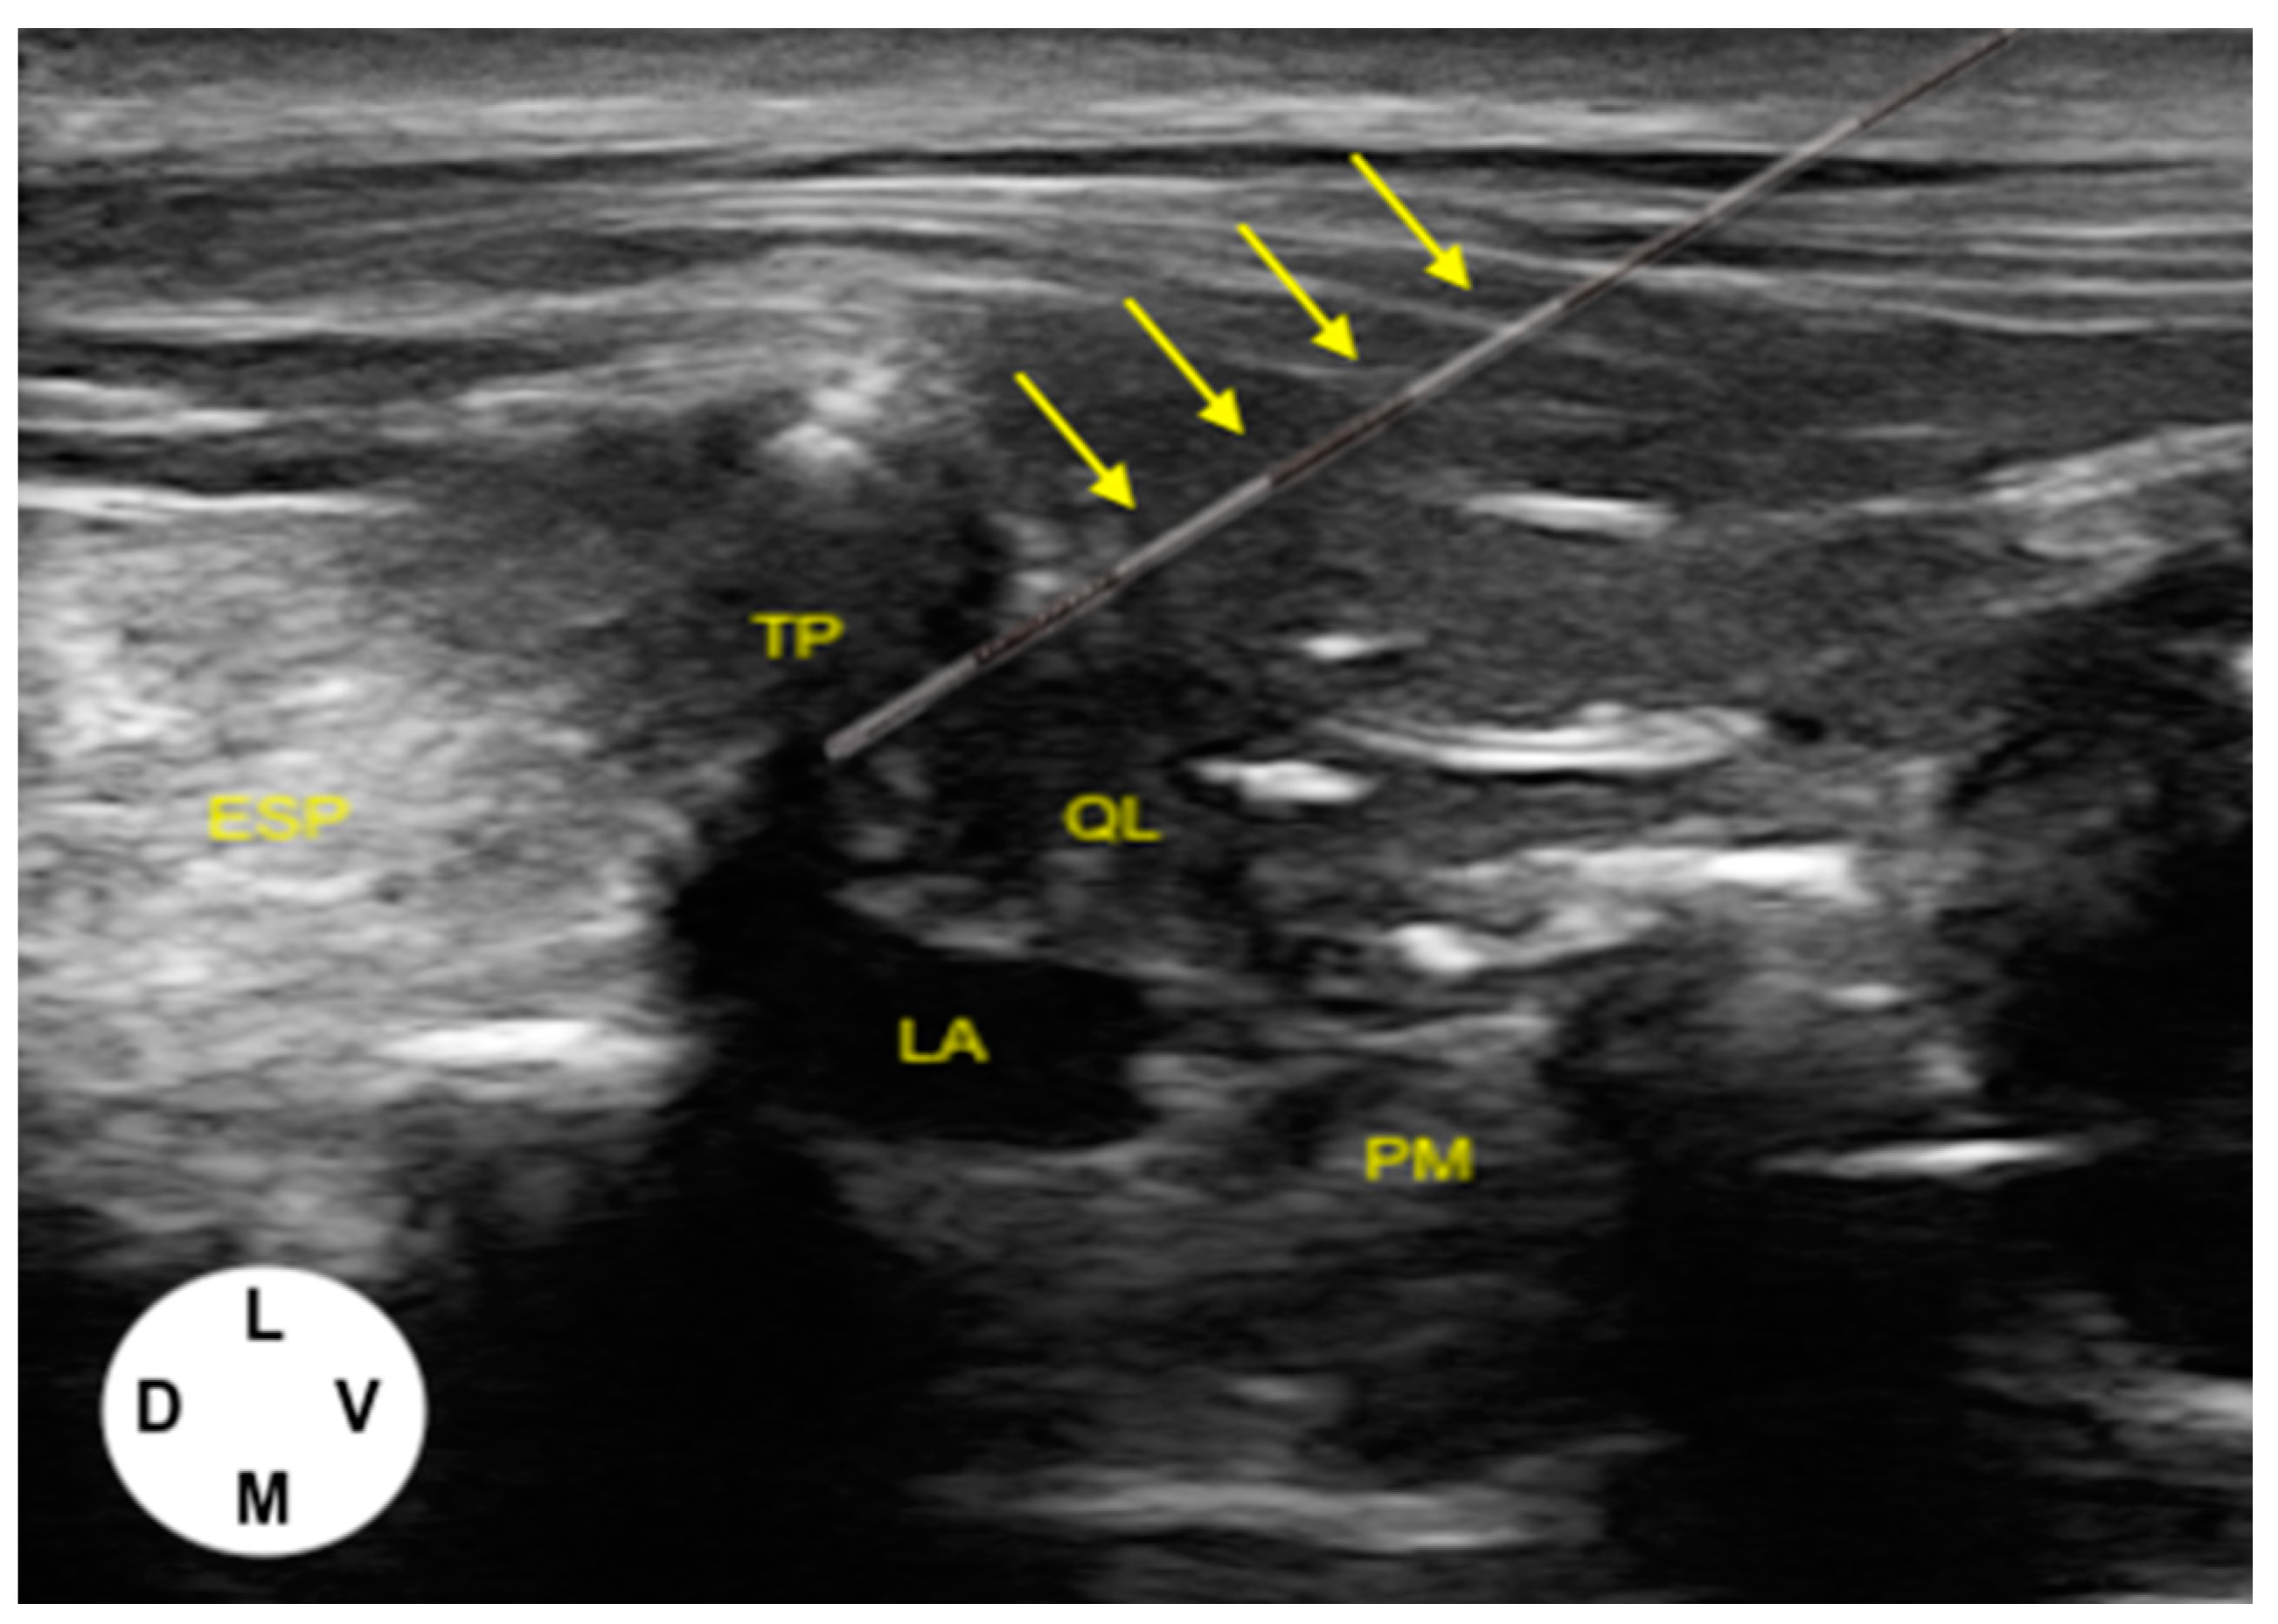

2.1.1. US-Guided Catheter Placement Technique

3.1.1. US-Guided Catheter Placement